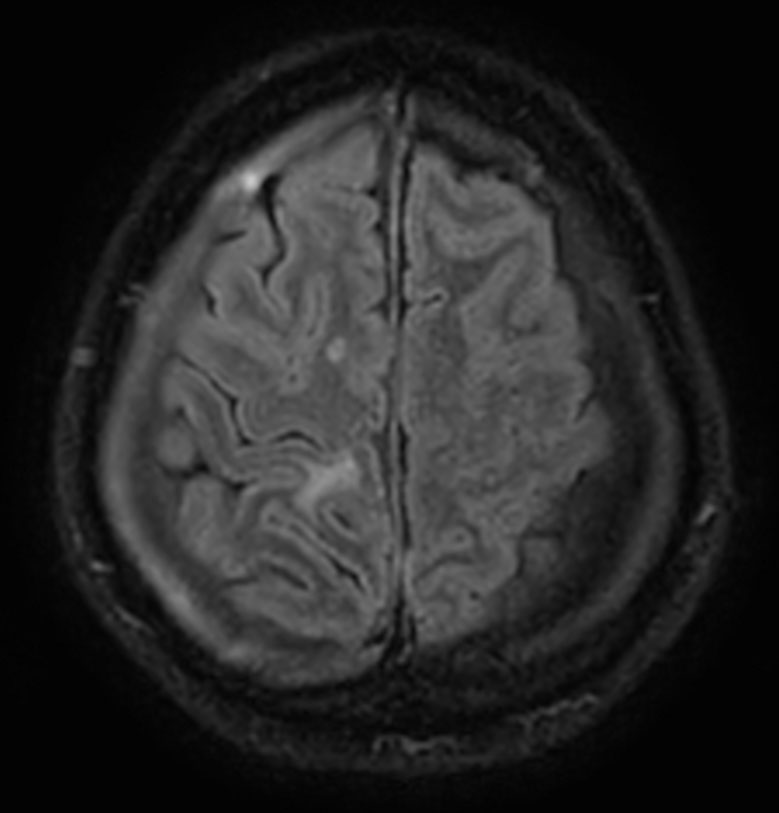

58 year old male with brain metastases, referred for post-op stereotactic radiotherapy of two targets to be irradiated with 27 Gy/3 Fx (Right parietal region) and 30 Gy/5 Fx (cerebellum). Patient underwent MRI simulation in the radiotherapy positioning mask on Ingenia MR-RT 1.5T.

Axial T2W 3D FLAIR